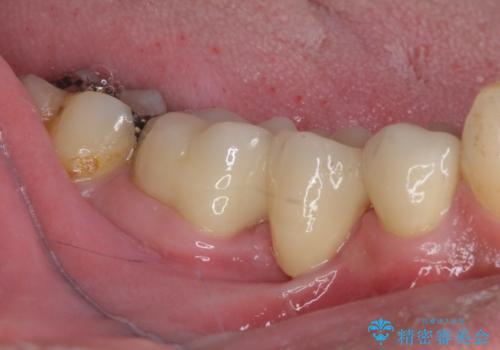

残念ながら抜歯が必要となりましたが、しっかりと診断を行ったことで、患者様も抜歯に納得していただけました。

抜歯後は痛みがあっという間に引き、ブリッジ補綴後は安定して咬めるようになりました。